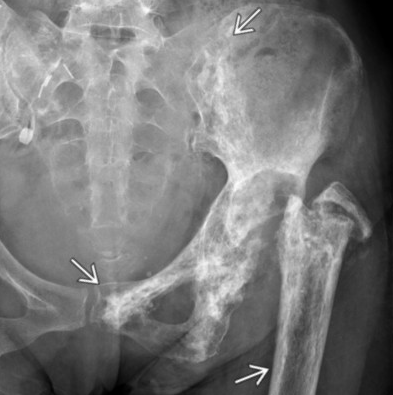

Hyperparathyroidism

• Decreased bone density

• Brown tumors

• Usually seen a multiple lytic lesions with additional lesions that look like they are healing concurrently

• Subperiosteal resorption along radial aspect of phalanges

• Subperiosteal reaction is basically resorption of bone under the periosteum and really looks like subtle inward curve (concave) appearance on the affected side, not very obviously unless very asymmetric on each side

• Acro-osteolysis

• Salt & pepper skull

• Superior and inferior rib notching may be seen - only this & rarely NF-1 that do both superior and inferior notching

• Bunch of other nonspecific shit that is basically all centered around bone being resorbed